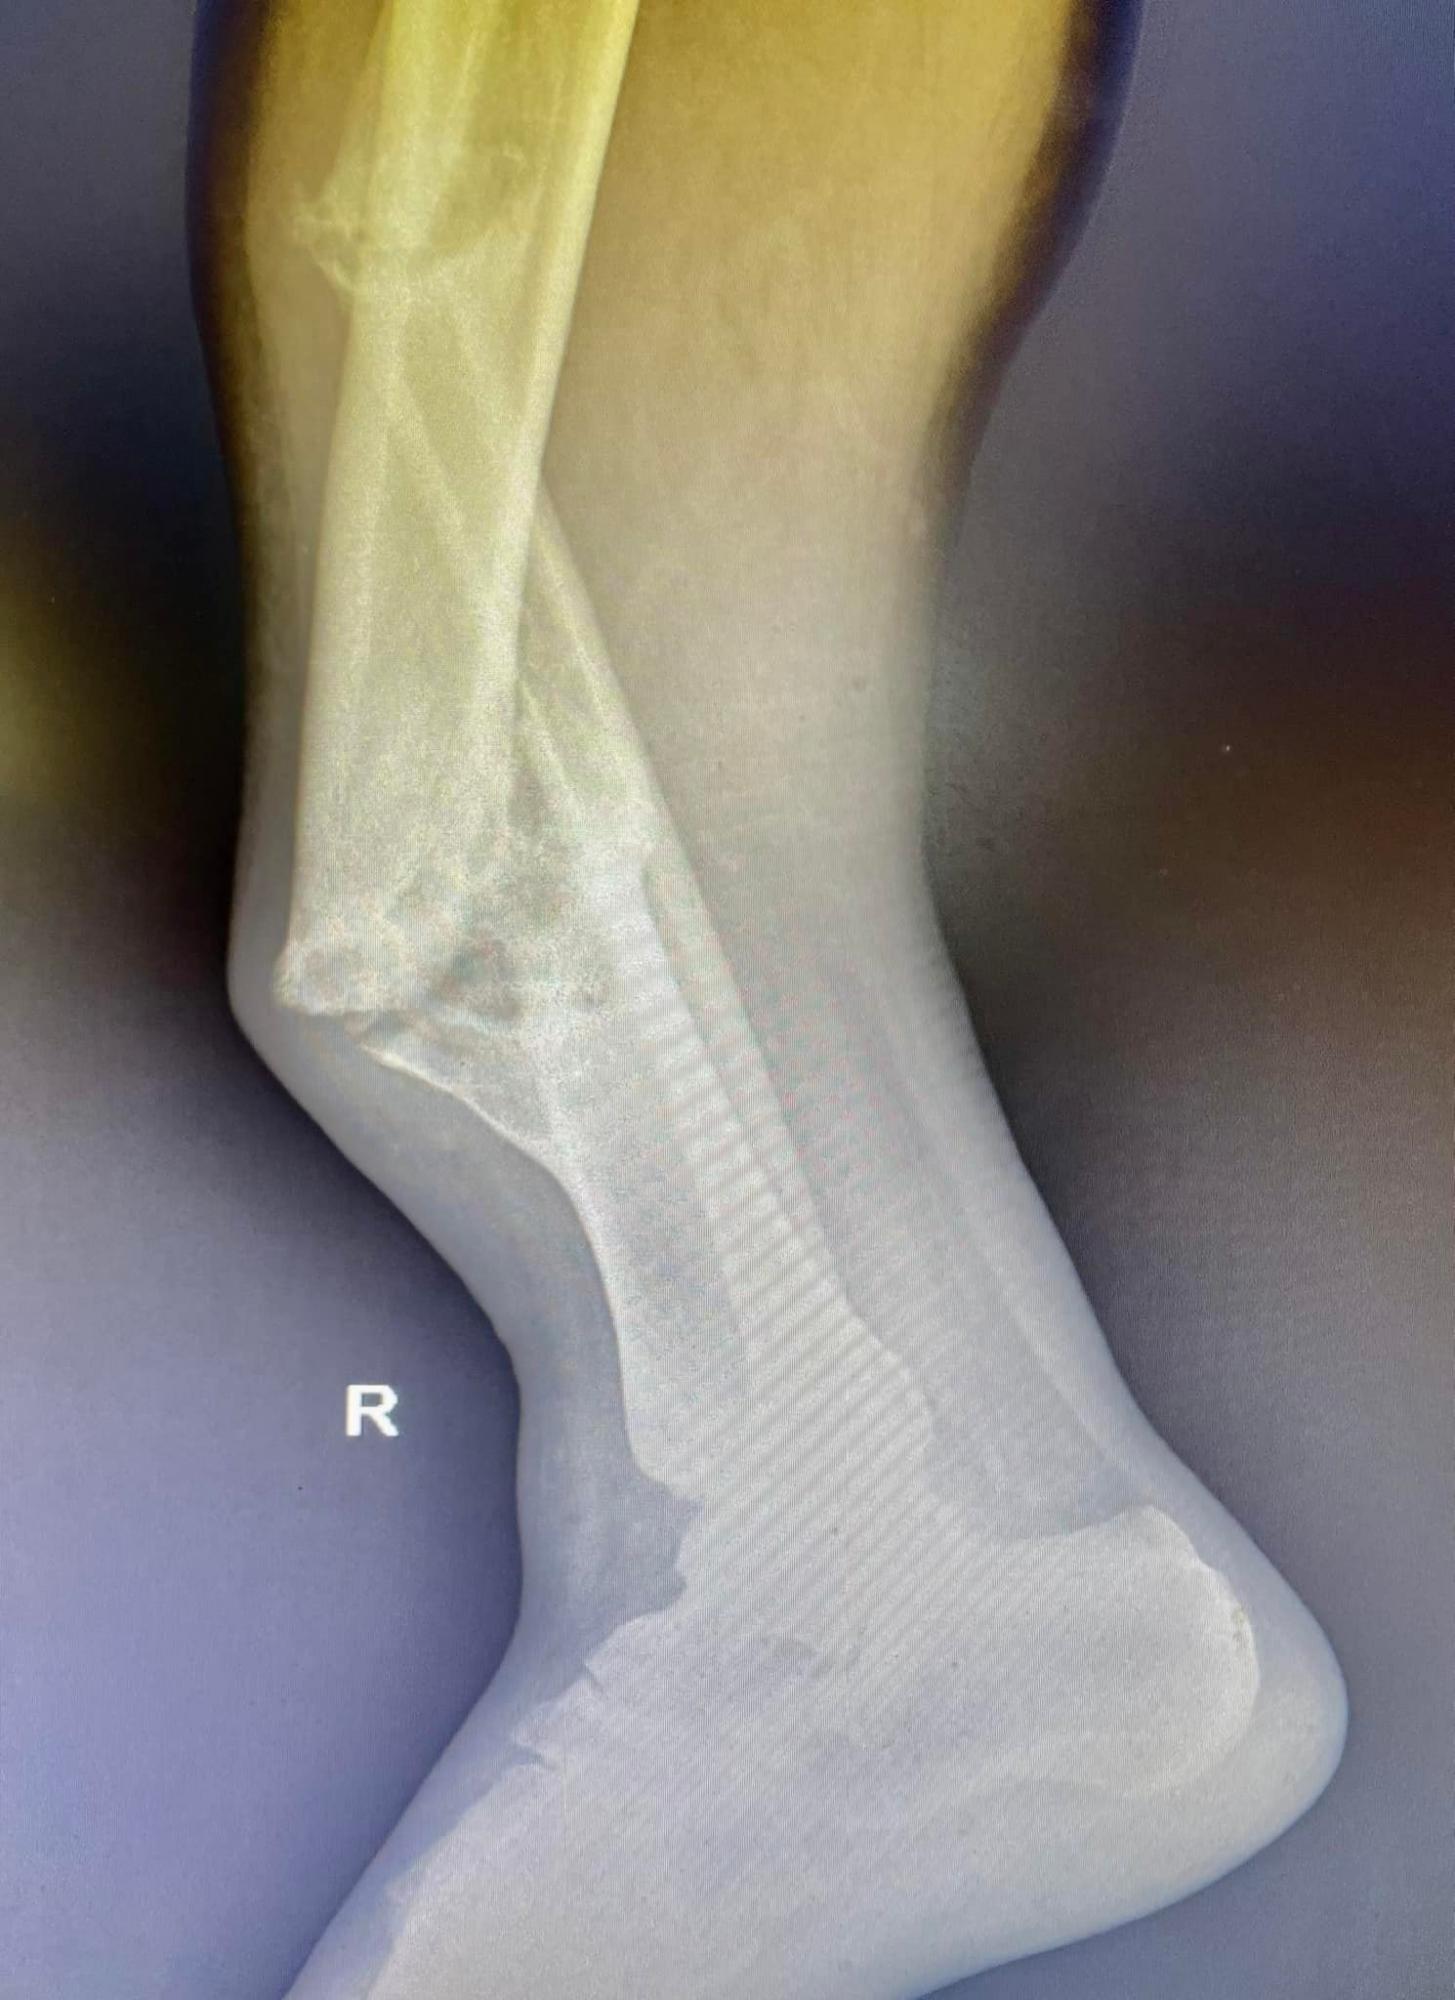

Во Львове хирурги провели операцию по удалению "фиктивного сустава" у жителя Славянска, который два года назад сломал ногу, отказался от лечения, и теперь его конечность сгибалась в разные стороны, а сам мужчина не мог ходить и уже потерял всякую надежду стать на ноги.

"Полгода он лежал в гипсе, надеясь, что кости срастутся своими силами. Этого не произошло, более того - на месте перелома у него сформировался "ненастоящий сустав". Нога потеряла сопротивляемость и начала сгибаться под разными углами. Павел потерял работу", - говорится в публикации.

Врачи отделения травматологии больницы Св. Луки Первого медобъединения Львова во время операции смогли избавиться от "фиктивного сустава", выровнять ось и длину концов и установить металлические конструкции (их оплатили благотворители).

После операции для полного восстановления ноги потребуется около 6 месяцев (фото: facebook.com/1tmolviv)